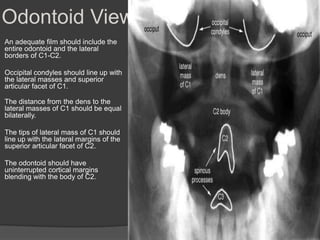

Odontoid View

An adequate film should include the

entire odontoid and the lateral

borders of C1-C2.

Occipital condyles should line up with

the lateral masses and superior

articular facet of C1.

The distance from the dens to the

lateral masses of C1 should be equal

bilaterally.

The tips of lateral mass of C1 should

line up with the lateral margins of the

superior articular facet of C2.

The odontoid should have

uninterrupted cortical margins

blending with the body of C2.